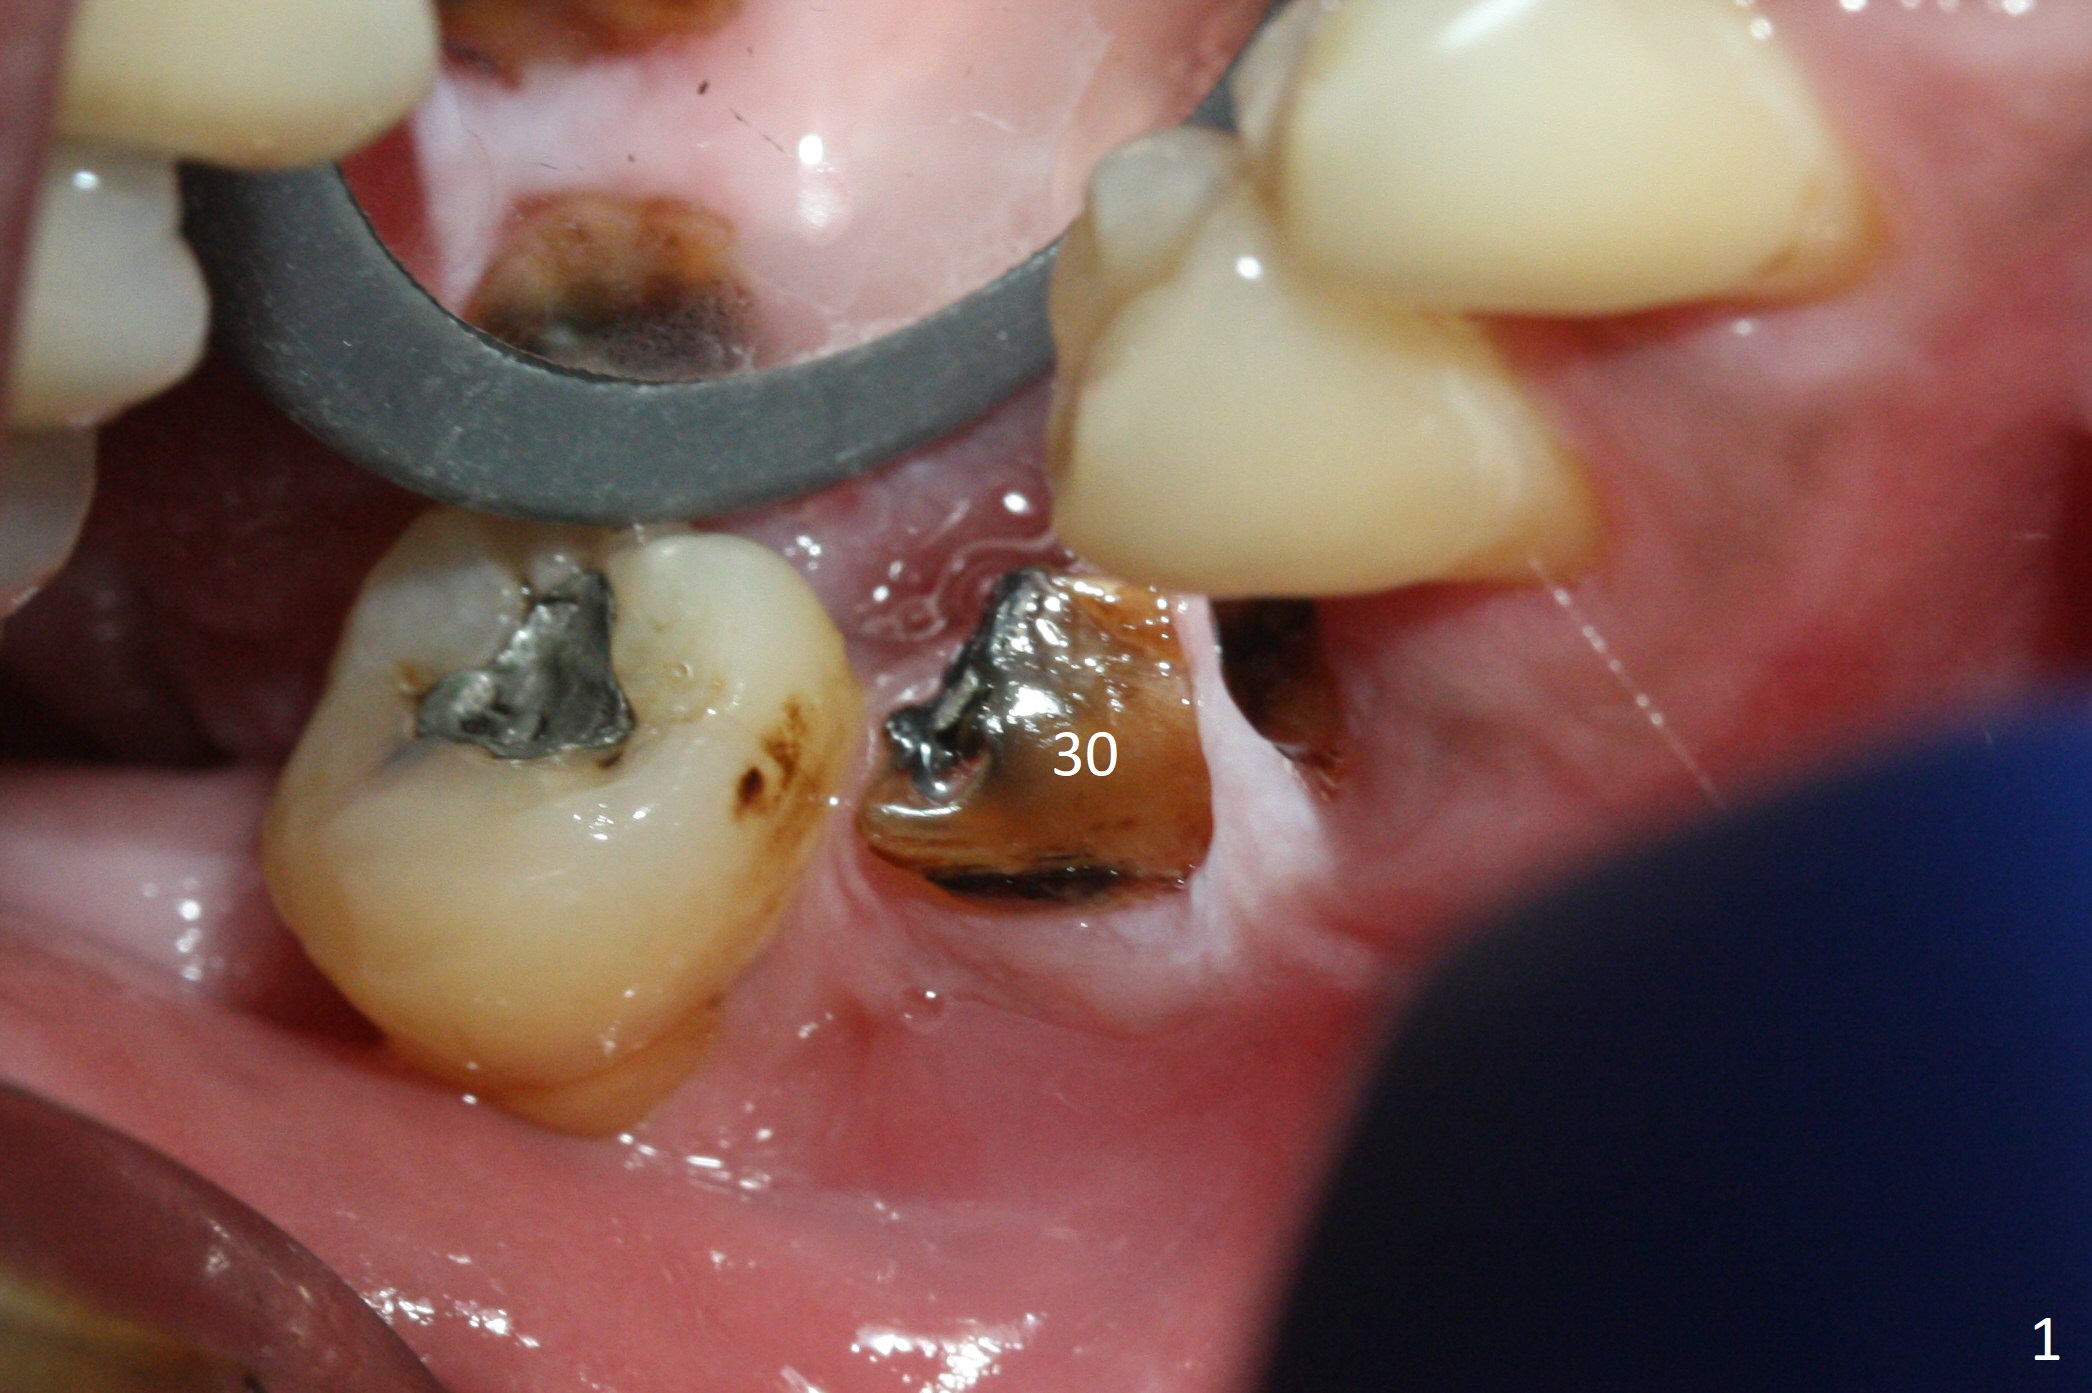

When the residual roots of the tooth #30 (Fig.1) are removed, the buccal crest is found ~ 2 mm apical to the lingual one (Fig.2 <); while the initial depth of osteotomy is 11.5 mm (yellow lines), the parallel pin is 10 mm long.  To place a 5x11.5 mm implant at the level of the buccal crest (Fig.4 (>45 Ncm)), subsequent osteotomy depth is 13 mm using the lingual crest as a landmark (Fig.3 (4 mm drill in place)).  After insertion of a 5.7x5.5(3) mm abutment, Vanilla Graft is placed (Fig.5 * with 2 mm buccal gap).  The abutment with a provisional is loose 4 months postop (Fig.6).   The permanent restoration is cemented 6 months postop.  The abutment screw is loose and fractured 8 and 11 months post cementation, respectively (Fig.7).  The fractured screw seems to be loose within the implant well and is easily re-winded out using Screw Removal Kit (sr-kit.html).  When the crown/abutment at #30 is loose 2nd time 1 year 7 months post cementation (Fig.8 taken post retightening), the screw at #19 fractures.  The tooth #2 needs a crown.  The patient cannot use the anterior teeth, since the teeth #8 and 9 have root fracture.  Can extraction and bone graft increase bone height?  The screw re-fractures 9 months later (Fig.9).  The dislodged crown is sectioned; the abutment is reseated completely (Fig.10) for a new crown. The tooth #2 needs RCT, B-U and crown, while the tooth #1 extraction (Fig.11).